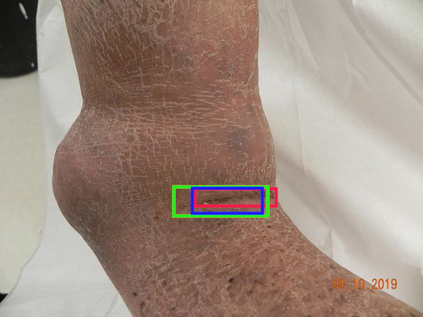

There has been a substantial amount of research on computer methods and technology for the detection and recognition of diabetic foot ulcers (DFUs), but there is a lack of systematic comparisons of state-of-the-art deep learning object detection frameworks applied to this problem. With recent development and data sharing performed as part of the DFU Challenge (DFUC2020) such a comparison becomes possible: DFUC2020 provided participants with a comprehensive dataset consisting of 2,000 images for training each method and 2,000 images for testing them. The following deep learning-based algorithms are compared in this paper: Faster R-CNN, three variants of Faster R-CNN and an ensemble method; YOLOv3; YOLOv5; EfficientDet; and a new Cascade Attention Network. For each deep learning method, we provide a detailed description of model architecture, parameter settings for training and additional stages including pre-processing, data augmentation and post-processing. We provide a comprehensive evaluation for each method. All the methods required a data augmentation stage to increase the number of images available for training and a post-processing stage to remove false positives. The best performance is obtained Deformable Convolution, a variant of Faster R-CNN, with a mAP of 0.6940 and an F1-Score of 0.7434. Finally, we demonstrate that the ensemble method based on different deep learning methods can enhanced the F1-Score but not the mAP. Our results show that state-of-the-art deep learning methods can detect DFU with some accuracy, but there are many challenges ahead before they can be implemented in real world settings.